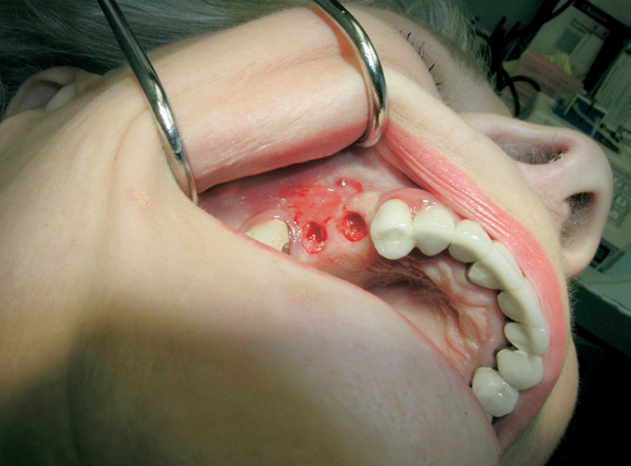

Velmi často je pro zavedení implantátu vzhledem k nedostatku kosti provést její doplnění tzv. augmentaci. Naše zařízení je zaměřené na doplnění nedostatečného množství kosti a používá celou řadu moderních postupů metod a matriálů. Velký význam pro úspěšné doplnění kosti hraje i dostatečné množství měkkých tkání – sliznice, která musí dodané množství kosti dokonale překrýt a nesmí ani tlakem způsobit jeho resorpci.

Jednou z nejmodernějších a velice šetrnou metodou pro získání dostatečného množství měkkých tkání je použití

osmotického hydrogelového expanderu.